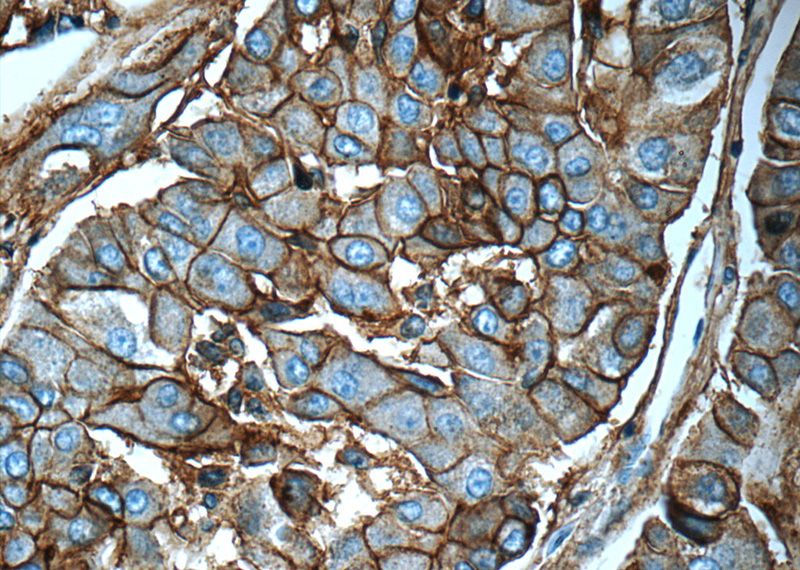

Immunohistochemical of paraffin-embedded human lung cancer using Catalog No:111587(ICAM-1 antibody) at dilution of 1:50 (under 25x lens)

Immunohistochemistry of paraffin-embedded human tonsillitis tissue slide using Catalog No:111587(ICAM-1 Antibody) at dilution of 1:50 (under 40x lens)

Immunohistochemistry of paraffin-embedded human liver cancer tissue slide using Catalog No:111587(ICAM-1 Antibody) at dilution of 1:50 (under 40x lens)